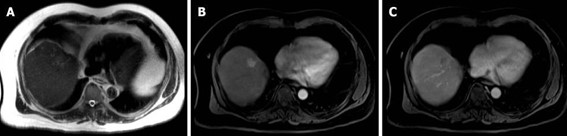

La hiperplasia nodular focal es el segundo tumor benigno más frecuente después del hemangioma. Tiene mayor incidencia en mujeres jóvenes. Histológicamente es un tumor hiperplásico que conserva los mismos componentes del tejido hepático normal, pero con una arquitectura alterada (hepatocitos normales + células de Kupffer + conductos biliares primitivos no conectados con la vía biliar normal). Presentan una cicatriz central de tejido fibroso con estructuras vasculares dilatadas y ectásicas. En la tomografía multicorte sin contraste intravenoso se evidencia como una lesión homogénea bien definida, hipo o isodensa con respecto al parénquima hepático. En la tomografía multicorte multifásica, después de la administración del medio de contraste, tiene un comportamiento típico.

- Fase arterial: reforzamiento intenso.

- Fase portal: es isodenso o ligeramente hiperdenso con respecto al parénquima.

- Fase tardía: lesión totalmente isodensa, no se visualiza, excepto porque puede producir efecto de masa sobre el parénquima adyacente.

La cicatriz central (Anexos 21 y 22), al estar menos vascularizada, no refuerza en fase arterial. Sin embargo, en fase tardía muestra hiperdensidad cuando ya el resto de la lesión se ha hecho isodensa.(18)